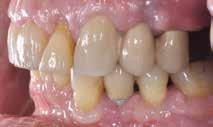

Patienttilfælde 1 (Fig. 1) er en 37-årig kvinde, henvist efter succesfuld behandling af stadie 3-parodontitis. Der er nu sundt

Før behandling

parodontium, ingen pocher over 4 mm, og både blødnings- og plakindeks er under 10 %. Patienten er motiveret for ortodontisk behandling, da hendes tænder er vandret over tid, delvist som følge af reduceret parodontium.

Der ses anterior trangstilling i begge kæber og overerupterede 1+1 og 2,1-1,2, hvilket resulterer i dybt bid med 2- tæt på ganepåbidning. Der er normale sidetandsrelationer, men der ses 5 mm horisontalt overbid (HOB) og 7 mm vertikalt

overbid (VOB). Papillen mellem 1+1 er betydeligt reduceret pga. fæstetab, og de mesialt kippede 1+1 har resulteret i en ”dark triangle”. Den facioorale funktion er for nuværende i.a. Panoramarøntgen (Fig. 1, I) viser marginalt knogletab i begge kæber og fravær af 8,7+7,8 og 8,7-8.

Objektivt anbefales behandling af det dybe bid, som ubehandlet forventes at forværres yderligere over tid. Patienten har ønske om behandling med æstetisk ortodontisk apparatur, alignere, og det vurderes muligt at behandle malokklusionen med alignere. Dog anbefales det generelt, at alignere undgås eller benyttes med væsentlige modifikationer af alignerens retention ved tandmobilitet, da dette ellers kan medføre jiggling, når aligneren tages af og på mange gange dagligt. På den anden side er der nogen evidens for, at alignerbehandling er associeret med bedre renhold og parodontal sundhed sammenlignet med fast apparatur (16).